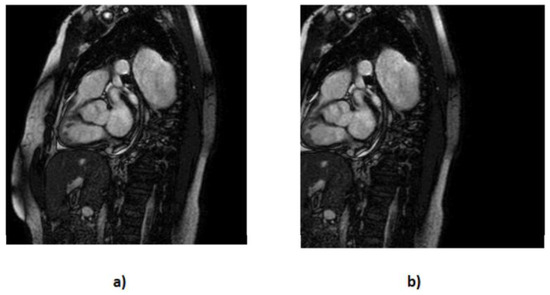

- We applied horizontal flipping (Figure 6), further diversifying our dataset by creating mirrored counterparts of existing images. With this process, we created 202 more MRIs and also introduced new perspectives for our models to learn from.